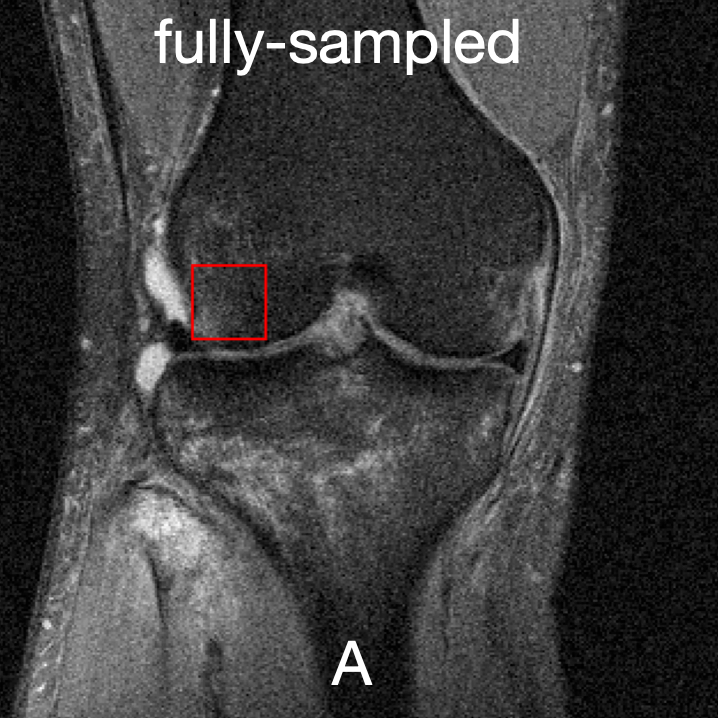

For a qualitative assessment of the results, we show some examples in figure˜0.B.1 for the UNet model and figure˜0.B.2 for the E2E-VarNet model of reconstructions where the attack was successful. These figures are structured as 2x2 panels of images where the first row displays the original and perturbed input samples and the second row displays the corresponding model-based reconstructions. Areas which we believe contain hallucinatory structures are highlighted in red.

We notice from LABEL:fig:unet-best1 and LABEL:fig:unet-best2 that the multi-coil images seem to be more vulnerable than the single-coil ones, in the sense that the resulting distortions are more severe for multi-coil data. The generated perturbations also seem easier to spot for single-coil data. This may be explained by the fact that perturbations in the multi-coil images can be more “spread out” across the coils, whereas with single-coil data this is not possible. This is consistent with the observation that vulnerability to adversarial examples increases with data dimensionality [14, 27]. Although we cannot compare to single-coil data for the E2E-VarNet, we do notice large distortions in LABEL:fig:varnet-best1 as well that go far beyond the boundaries of our inserted detail. On the multi-coil brain data, the hallucinations seem less severe for both models compared to the knee data, but the distortions can still be significant as they tend to resemble non-existent sulci. For knee images, the distortions appear to substantially change the structure of the knee joint, especially on multi-coil data.

We conclude that the adversarially perturbed samples can lead to realistic reconstructions which exhibit biologically plausible distortions that could mislead expert interpretation, and that the insertion of the artificial detail will often cause further distortion beyond the original target region. For both models, this is especially apparent in the multicoil knee data, where the shape of the knee joint tends to change significantly when the detail is inserted.